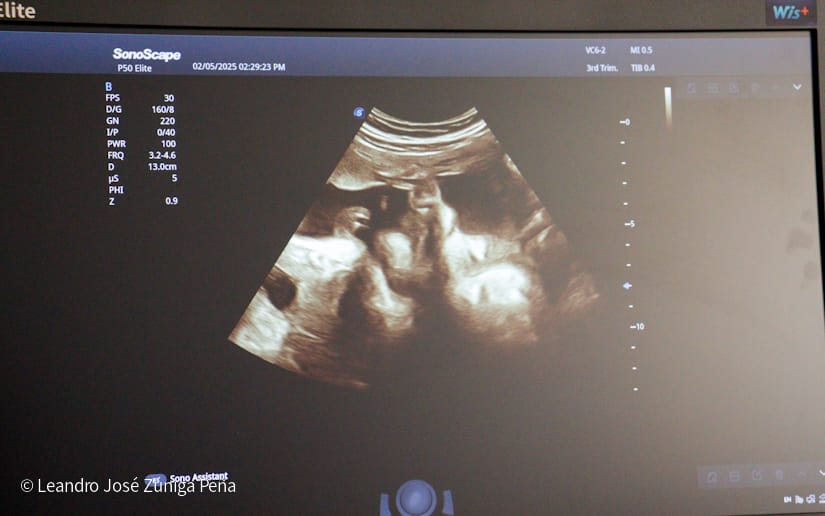

“Con estos ultrasonidos, que son de alta tecnología en el país, estamos completando 32 equipos de ultrasonido que están ubicados en las diferentes unidades de salud. Estos últimos 6 equipos nos van a permitir hacer diagnóstico de manera preventiva a la mujer embarazada, tenemos recursos humanos calificados, médicos especialistas formados por nuestro gobierno, en nuestro país, que tienen todos los conocimientos necesarios para poder hacer diagnóstico de anomalías congénitas, diagnóstico prenatal de alteraciones en la embarazada y en el feto y poder hacer prevención de la preclancia, el parto prematuro, la restricción del crecimiento fetal o bajo peso, que son morbilidades que afectan a nuestras embarazadas y a nuestro recién nacido, de igual manera, la tecnología volumétrica que se ha adquirido en estos equipos como el 3D y el 4D permite obtener mejores imágenes de anomalías congénitas para que estas pacientes que son captadas en estas unidades puedan ser referidas al Bertha Calderón”, explicó el especialista.